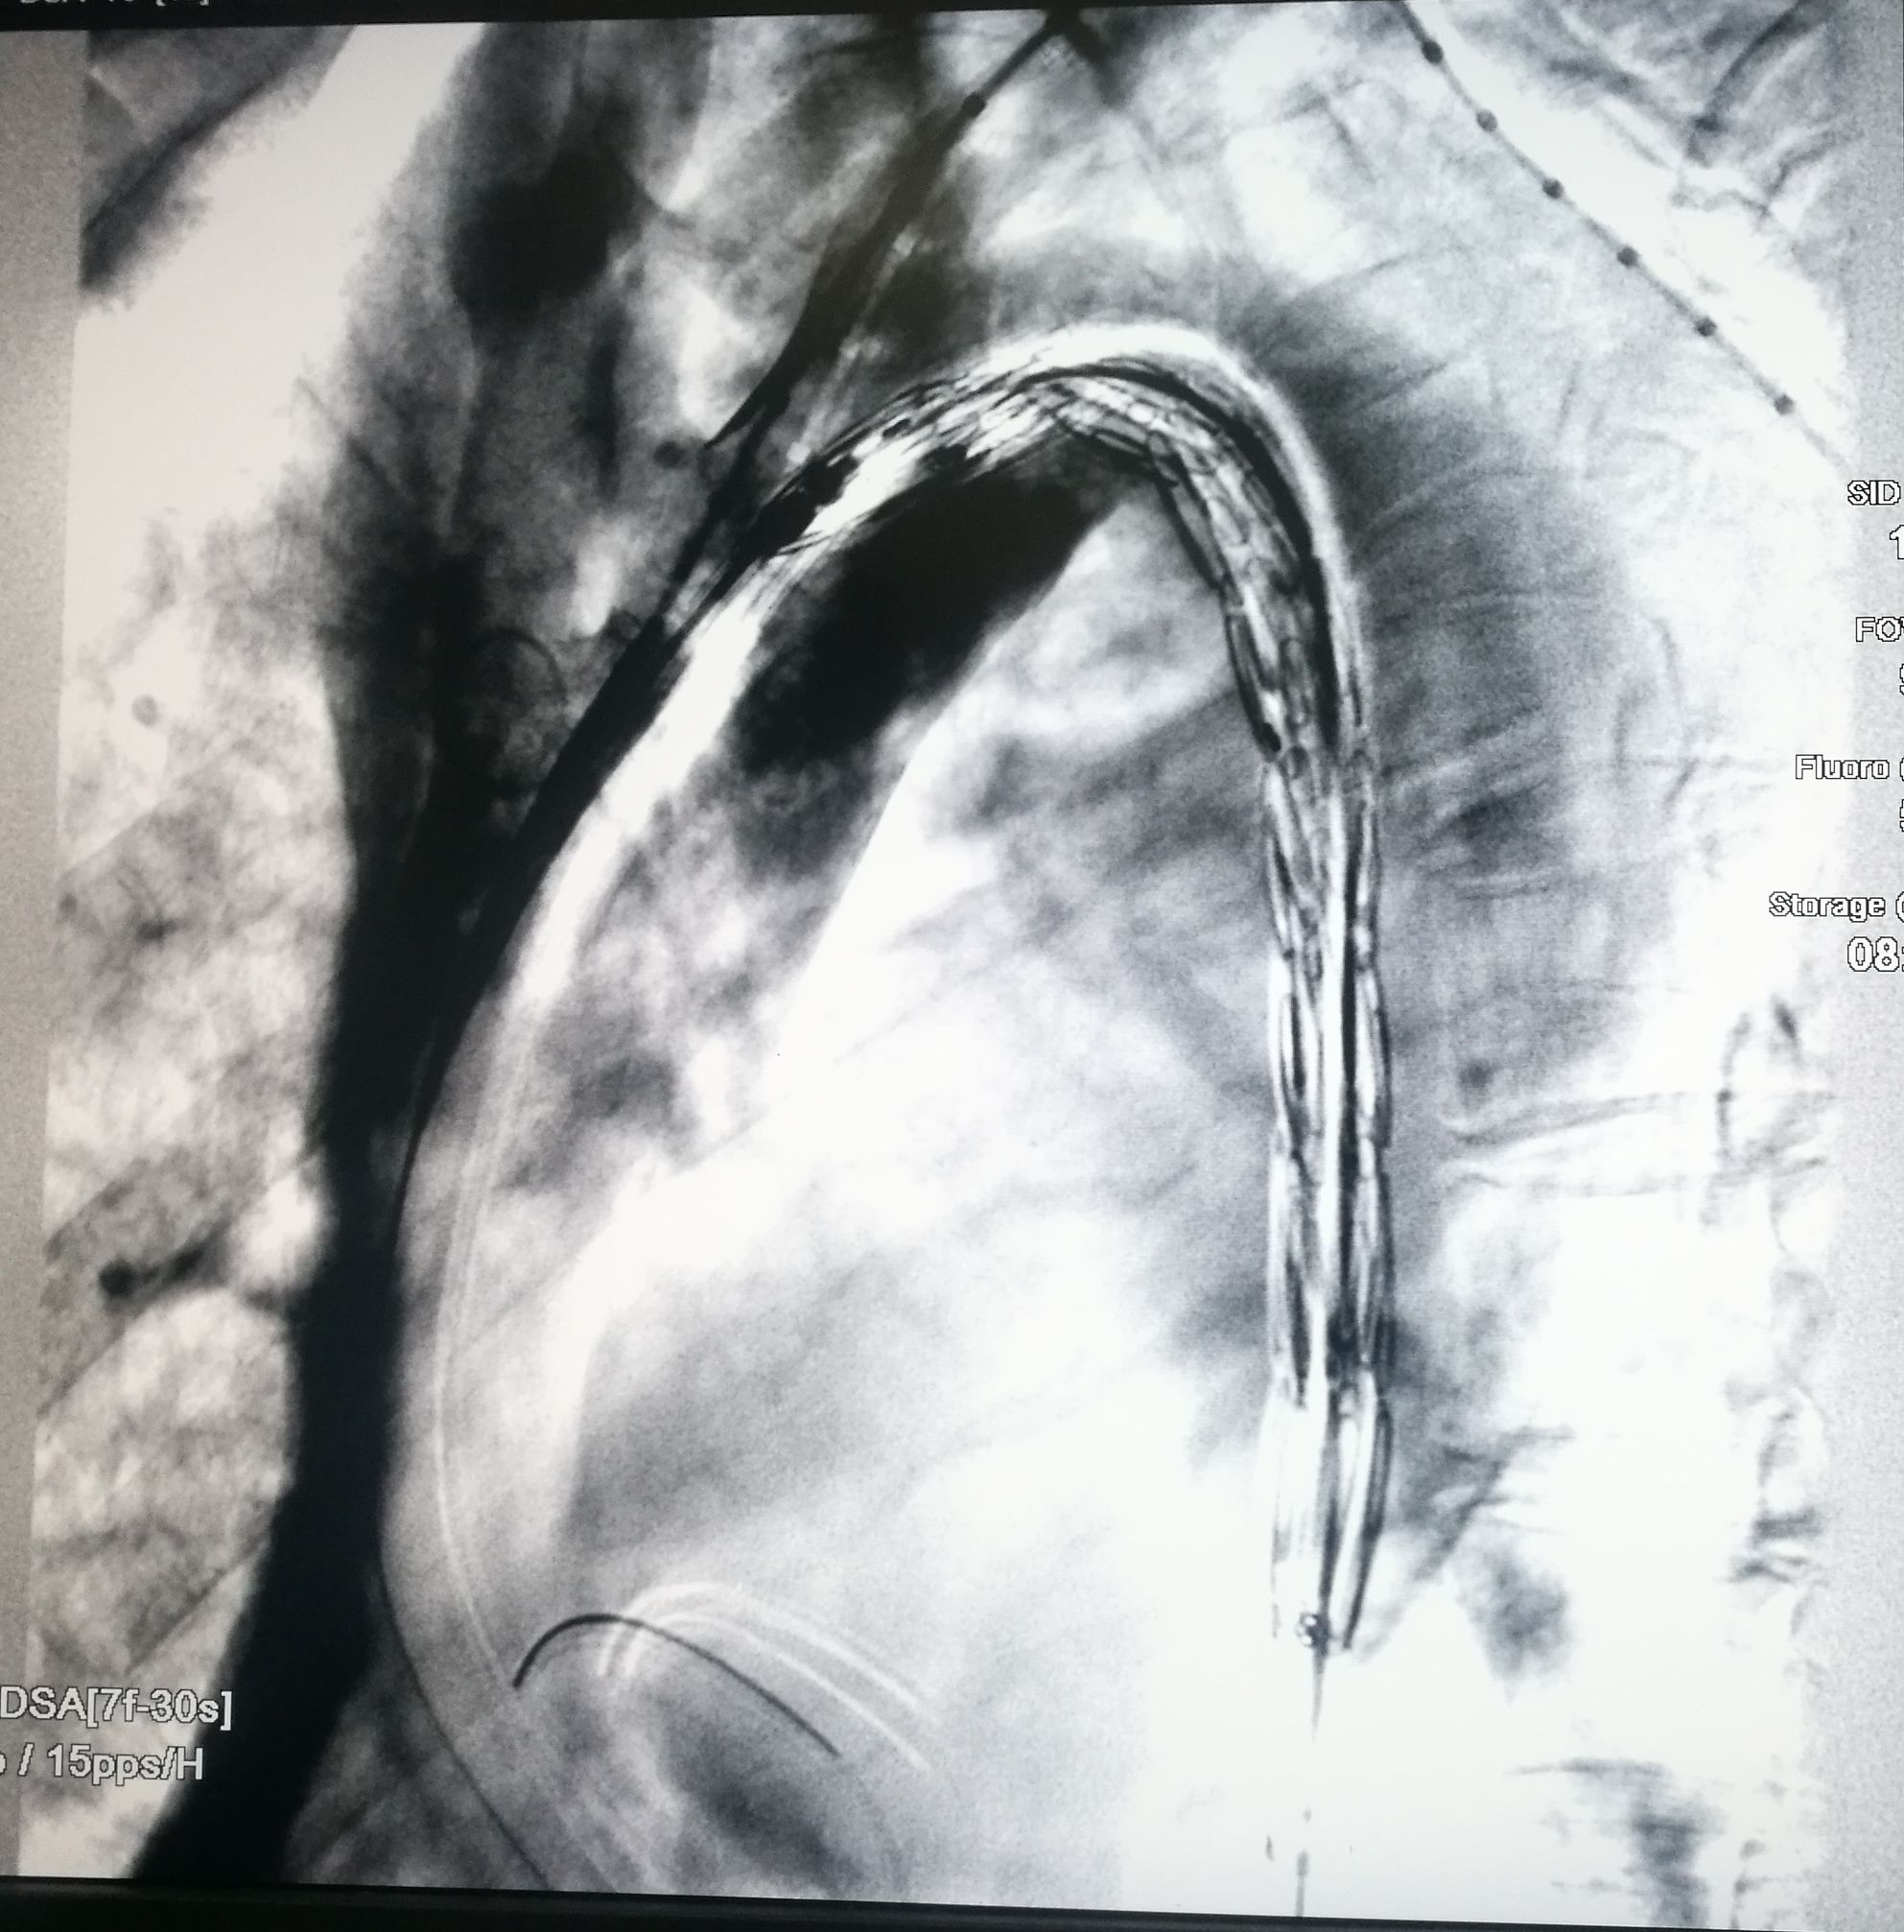

手术在局麻下进行,经右股动脉穿刺置管到升主,经左桡动脉穿刺植入金标猪尾导管,造影,为确认真假腔,加做右前斜位造影,确认股动脉导管在真腔内,测量后植入覆膜支架。由于扭曲严重(腹主,膈肌附近,弓降),支架最初并未贴服大湾侧,支架送过锁骨下动脉后适当回撤,请拉释放导丝,此时支架整体向大弯侧轻微移动,考虑应力已经得到缓解。完全释放支架,定位良好,封堵完全无内漏。

尽管有加硬导丝,但从二维影像上看,支架并未贴着大弯侧走行